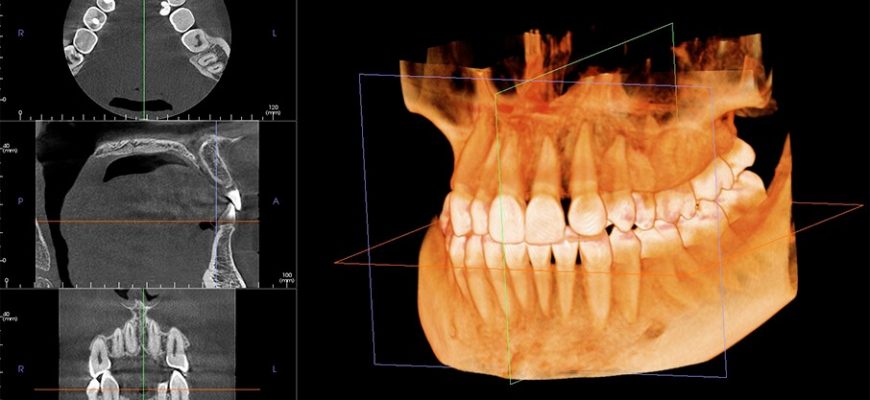

ИИ в стоматологии: Революция в анализе КТ и 3D планировании Стоматология, как и многие другие области медицины, переживает сейчас период бурного развития

ИИ в стоматологии: от снимка к диагнозу ⎻ личный опыт анализа КТ Приветствую вас, дорогие читатели! Сегодня мы погрузимся в захватывающий мир применения